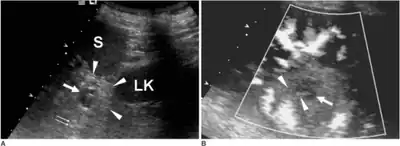

| Ultrasound image of intrapancreatic accessory spleen | |